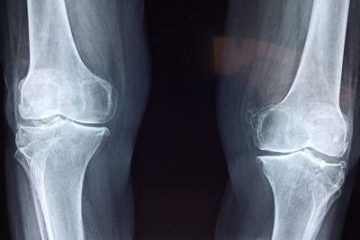

Présentation des résultats d'un traitement par phagothérapie - infection ostéo articulaire